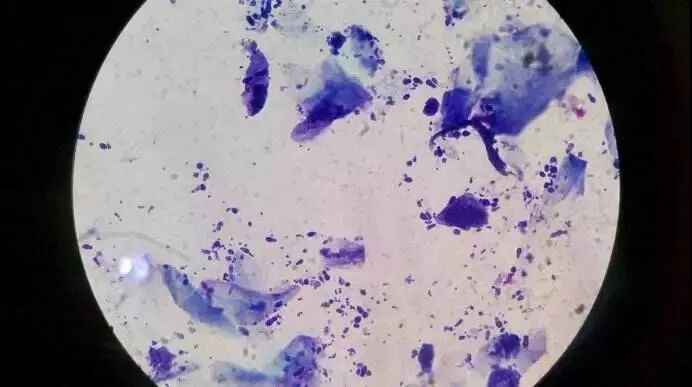

马拉色菌属的真菌跟脂溢性皮炎也有很大的关系,虽然起因不是它们,但是它们会吃掉皮脂,就地分泌代谢物,会改变角质层的结构。